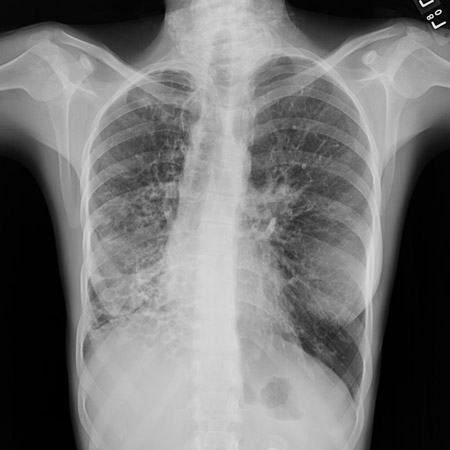

Radiografía de tórax con falta de conicidad normal que produce una línea de tranvía en un paciente con bronquiectasias

De la colección personal de Dr S.M. Bhorade, University of Chicago Medical Center; utilizada con autorización